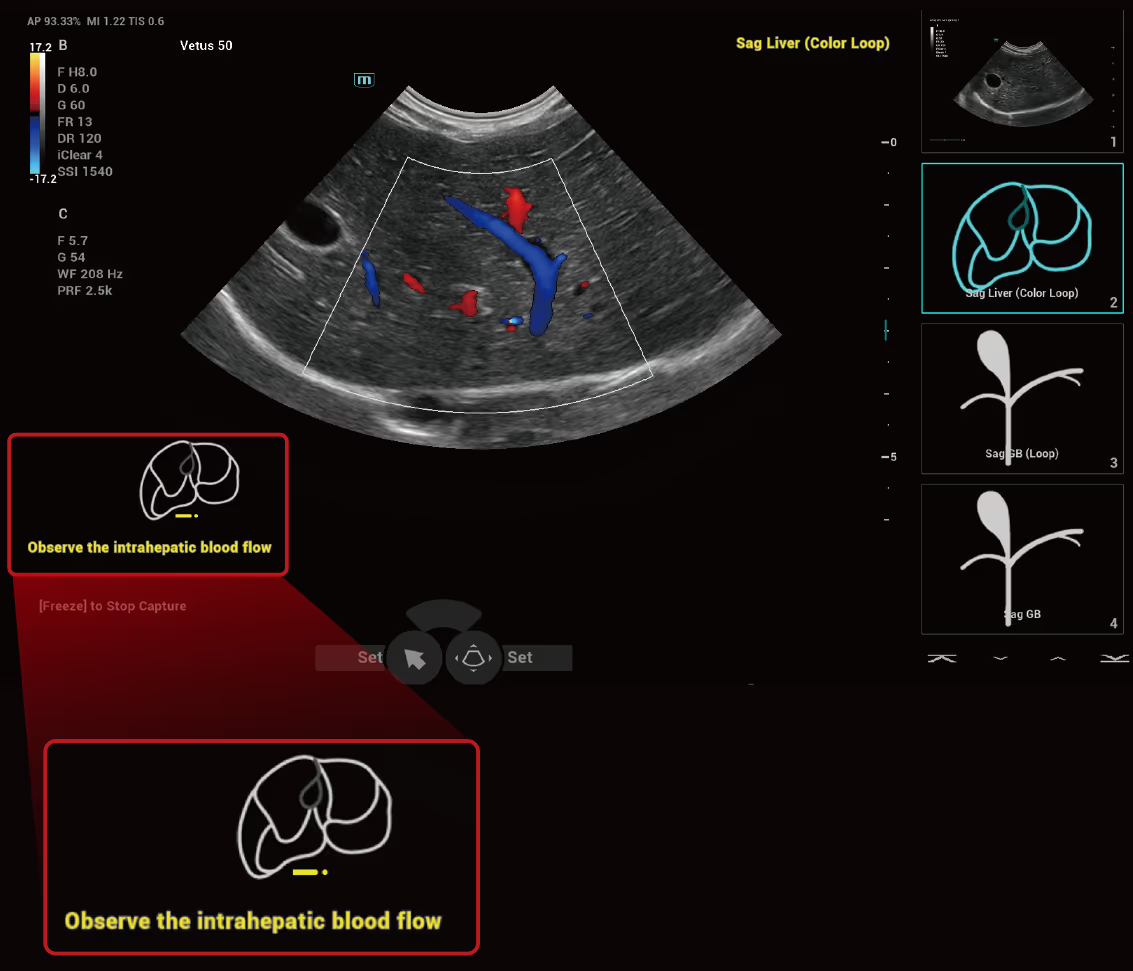

Standart protokoller her klinik uygulama için yetkin ve tutarlı bir taramayı destekler.

iMeasure, olası veya şüphelenilen klinik durumları anında ekranda önerir.